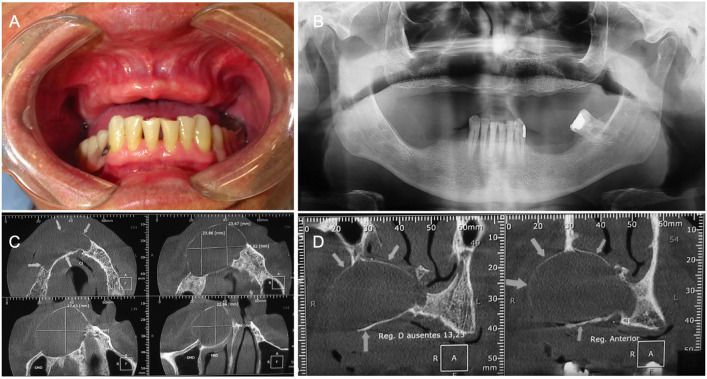

Background: Glandular Odontogenic Cyst (GOC) is a rare benign lesion with unique histological features, and more aggressive growth pattern compared to other odontogenic cysts. GOC typically presents as an asymptomatic, slow-growing swelling, predominantly affecting middle-aged males and often localized in the anterior mandible. This report details three cases of GOC affecting the maxilla.

Case report: Case 1 presented a GOC mimicking a residual cyst in the maxilla. Case 2 involved a GOC located within the maxillary sinus. Case 3 showed a multilocular radiolucent GOC in the anterior maxilla. All cases were treated by surgery, and the diagnosis was confirmed through microscopic examination.